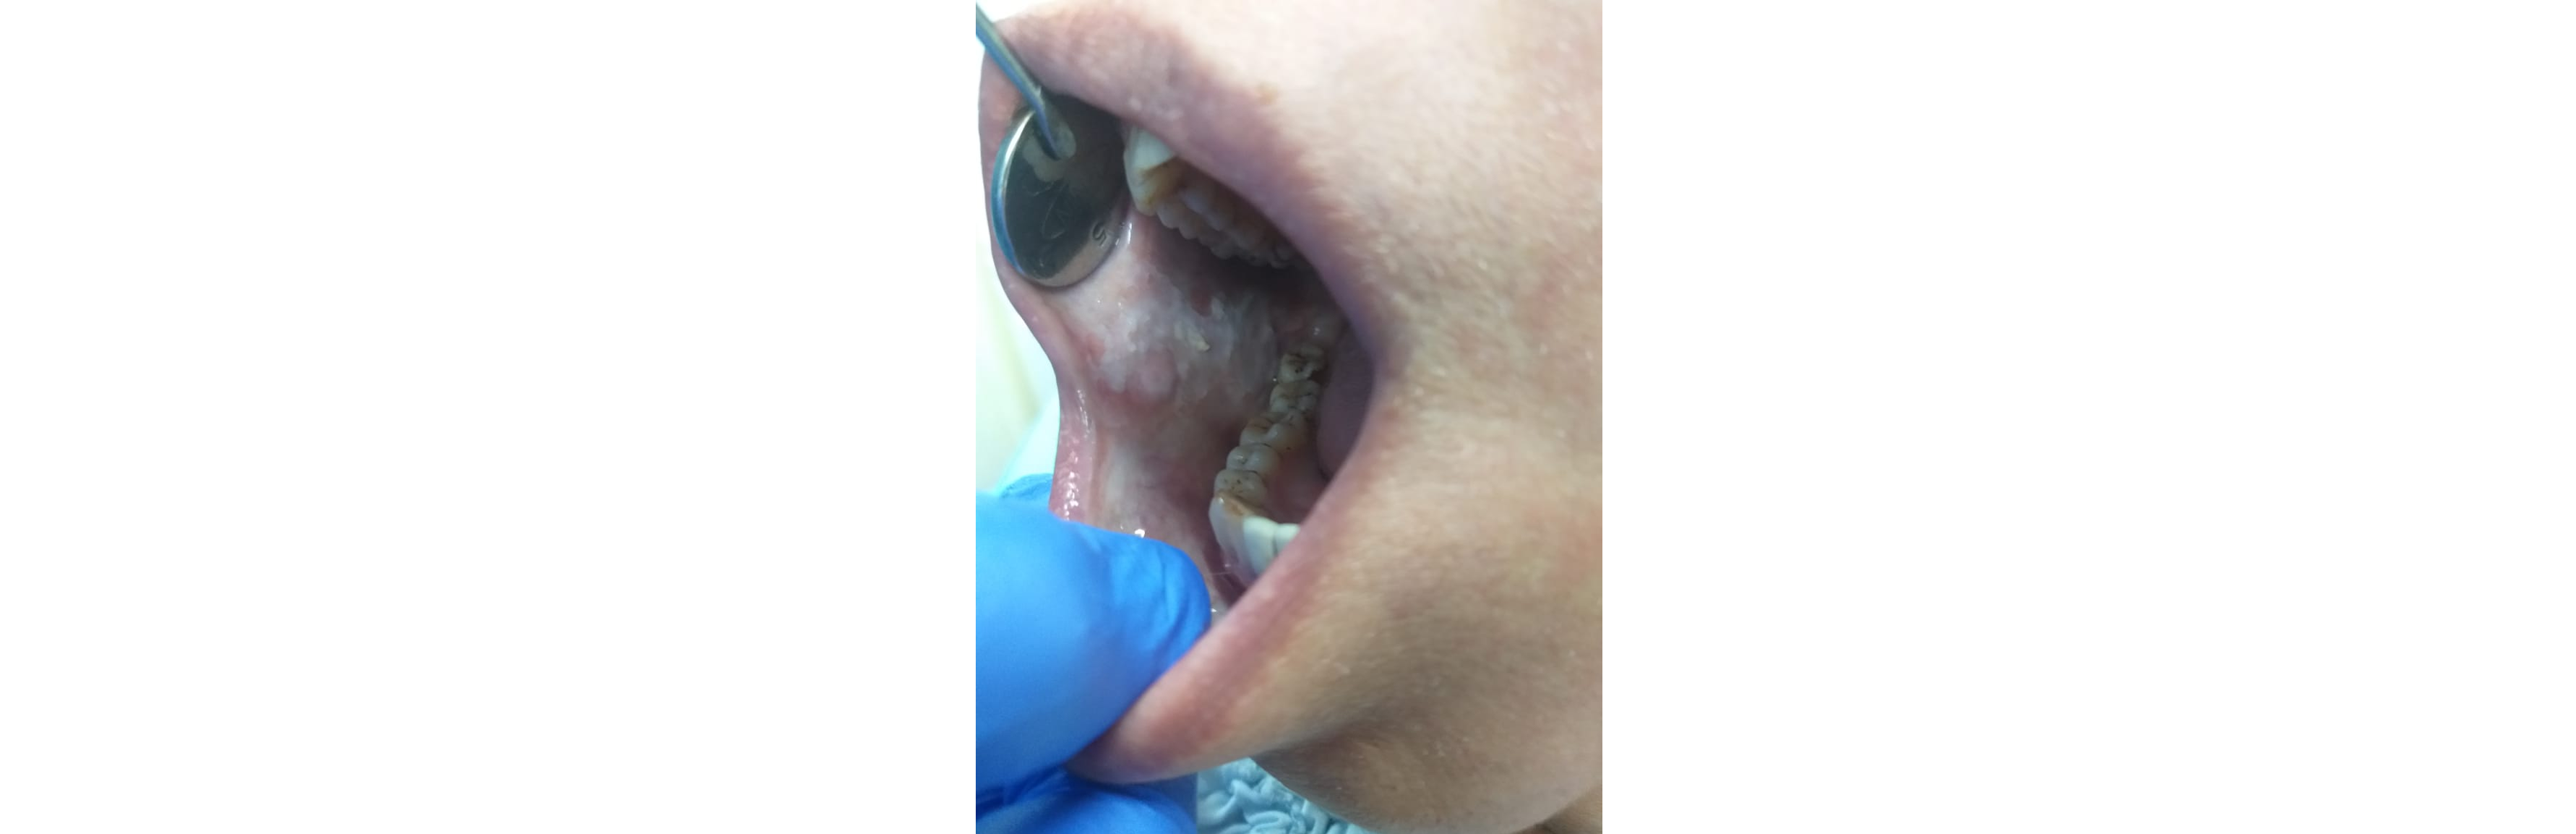

Lesions of the mouth, lip, and tongue encompass a range of conditions that can affect oral health and comfort. Treatment for mouth ulcers and sores involves identifying and addressing the underlying causes, which can include nutritional deficiencies, stress, or systemic diseases. Effective management often includes topical treatments, lifestyle modifications, and in some cases, medications to alleviate pain and promote healing. Ensuring that these lesions are properly evaluated is crucial to rule out more serious conditions and provide appropriate care.